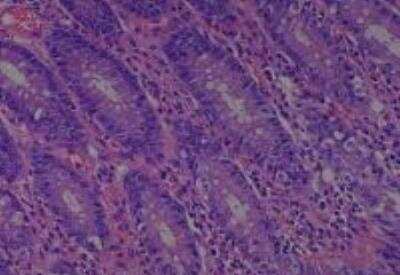

Hematoxylin & Eosin Stain: Human Common Tissue MicroArray (Normal Adjacent) [NBP2-30215] - 103. Stomach